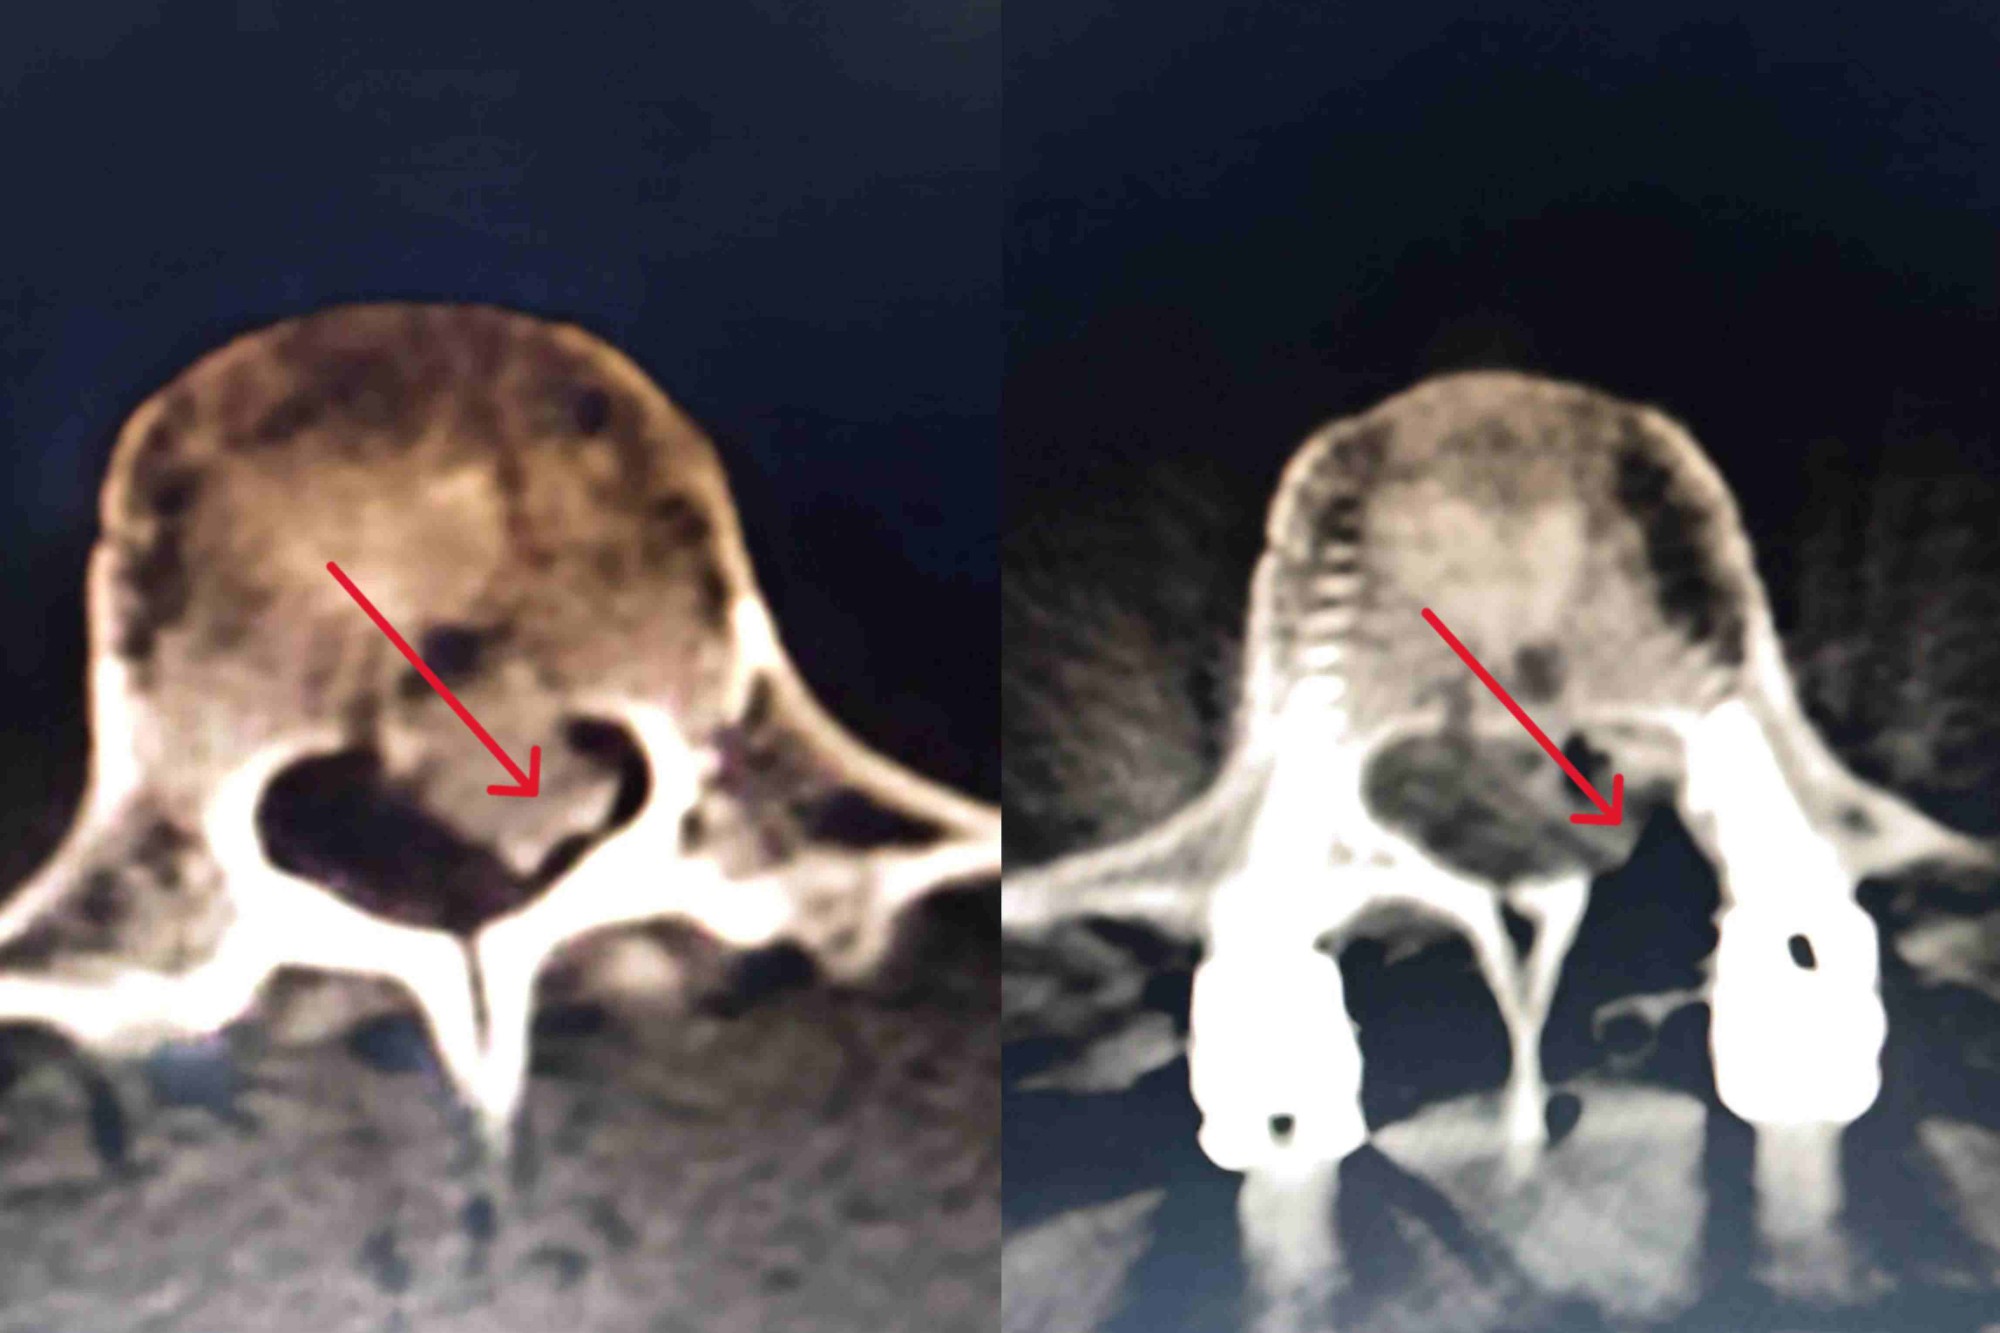

患者因高处坠落导致右足先着地,巨大冲击力造成全身多发伤,被紧急送入院。入院时已呈意识模糊、血压骤降、呼吸急促等危重状态。急诊CT明确诊断为右踝关节粉碎性骨折、骨盆骨折、气胸以及腰1、腰3椎体压缩性骨折,凝血功能提示早期DIC伴失血性休克,生命指标濒临危急值。医院立即启动危重患者救治预案,神经外科、脊柱外科、胸外科、输血科等多学科专家迅速集结会诊,为患者制定了周密的个体化救治方案。

经过数日积极救治,患者休克得以纠正,DIC指标恢复正常,气胸改善,生命体征趋于稳定,已成功度过危险期。病情稳定后,神经外科唐乐剑主任医师团队经全面评估与讨论,为这位年轻患者实施了T12~L4椎弓根固定术联合椎管内骨折碎片取出术。手术顺利完成,有效修复了腰椎结构,为患者日后功能康复奠定了坚实基础。